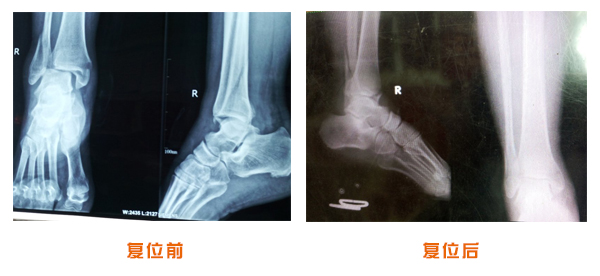

踝關節脫位骨折治療前后對比

復位前后對比